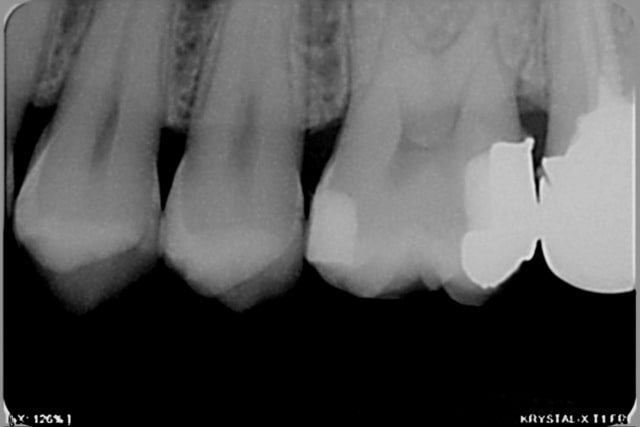

Voici l’exemple d’un cas fait comme ça hier, un cas un peu limite puisque j’ai presque pu passer avec une matrice et un coin classique, mais je n’arrivais pas à bien sertir la marge pour être étanche. On peut rattraper des trucs plus sous gingivaux que ça avec ces matrices bananes.

et deux exemples en radios de cas similaires, un peu plus sous gingivaux d'ailleurs

T'as pas oublier un truc au distal de la 5 ? Sur la radio on dirait une carie...

je sais, c'est pour ça que j'ai refait le composite mésial sur la 6, vérifier si il y avait ou pas une carie distale sur la 5